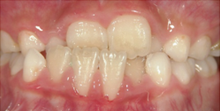

叢生(そうせい)

顎に歯が並びきらずに、重なって生えたりでこぼこになっている状態。見た目への影響や、

磨き残しが増えてしまう事でむし歯や歯周病になりやすい原因になります。